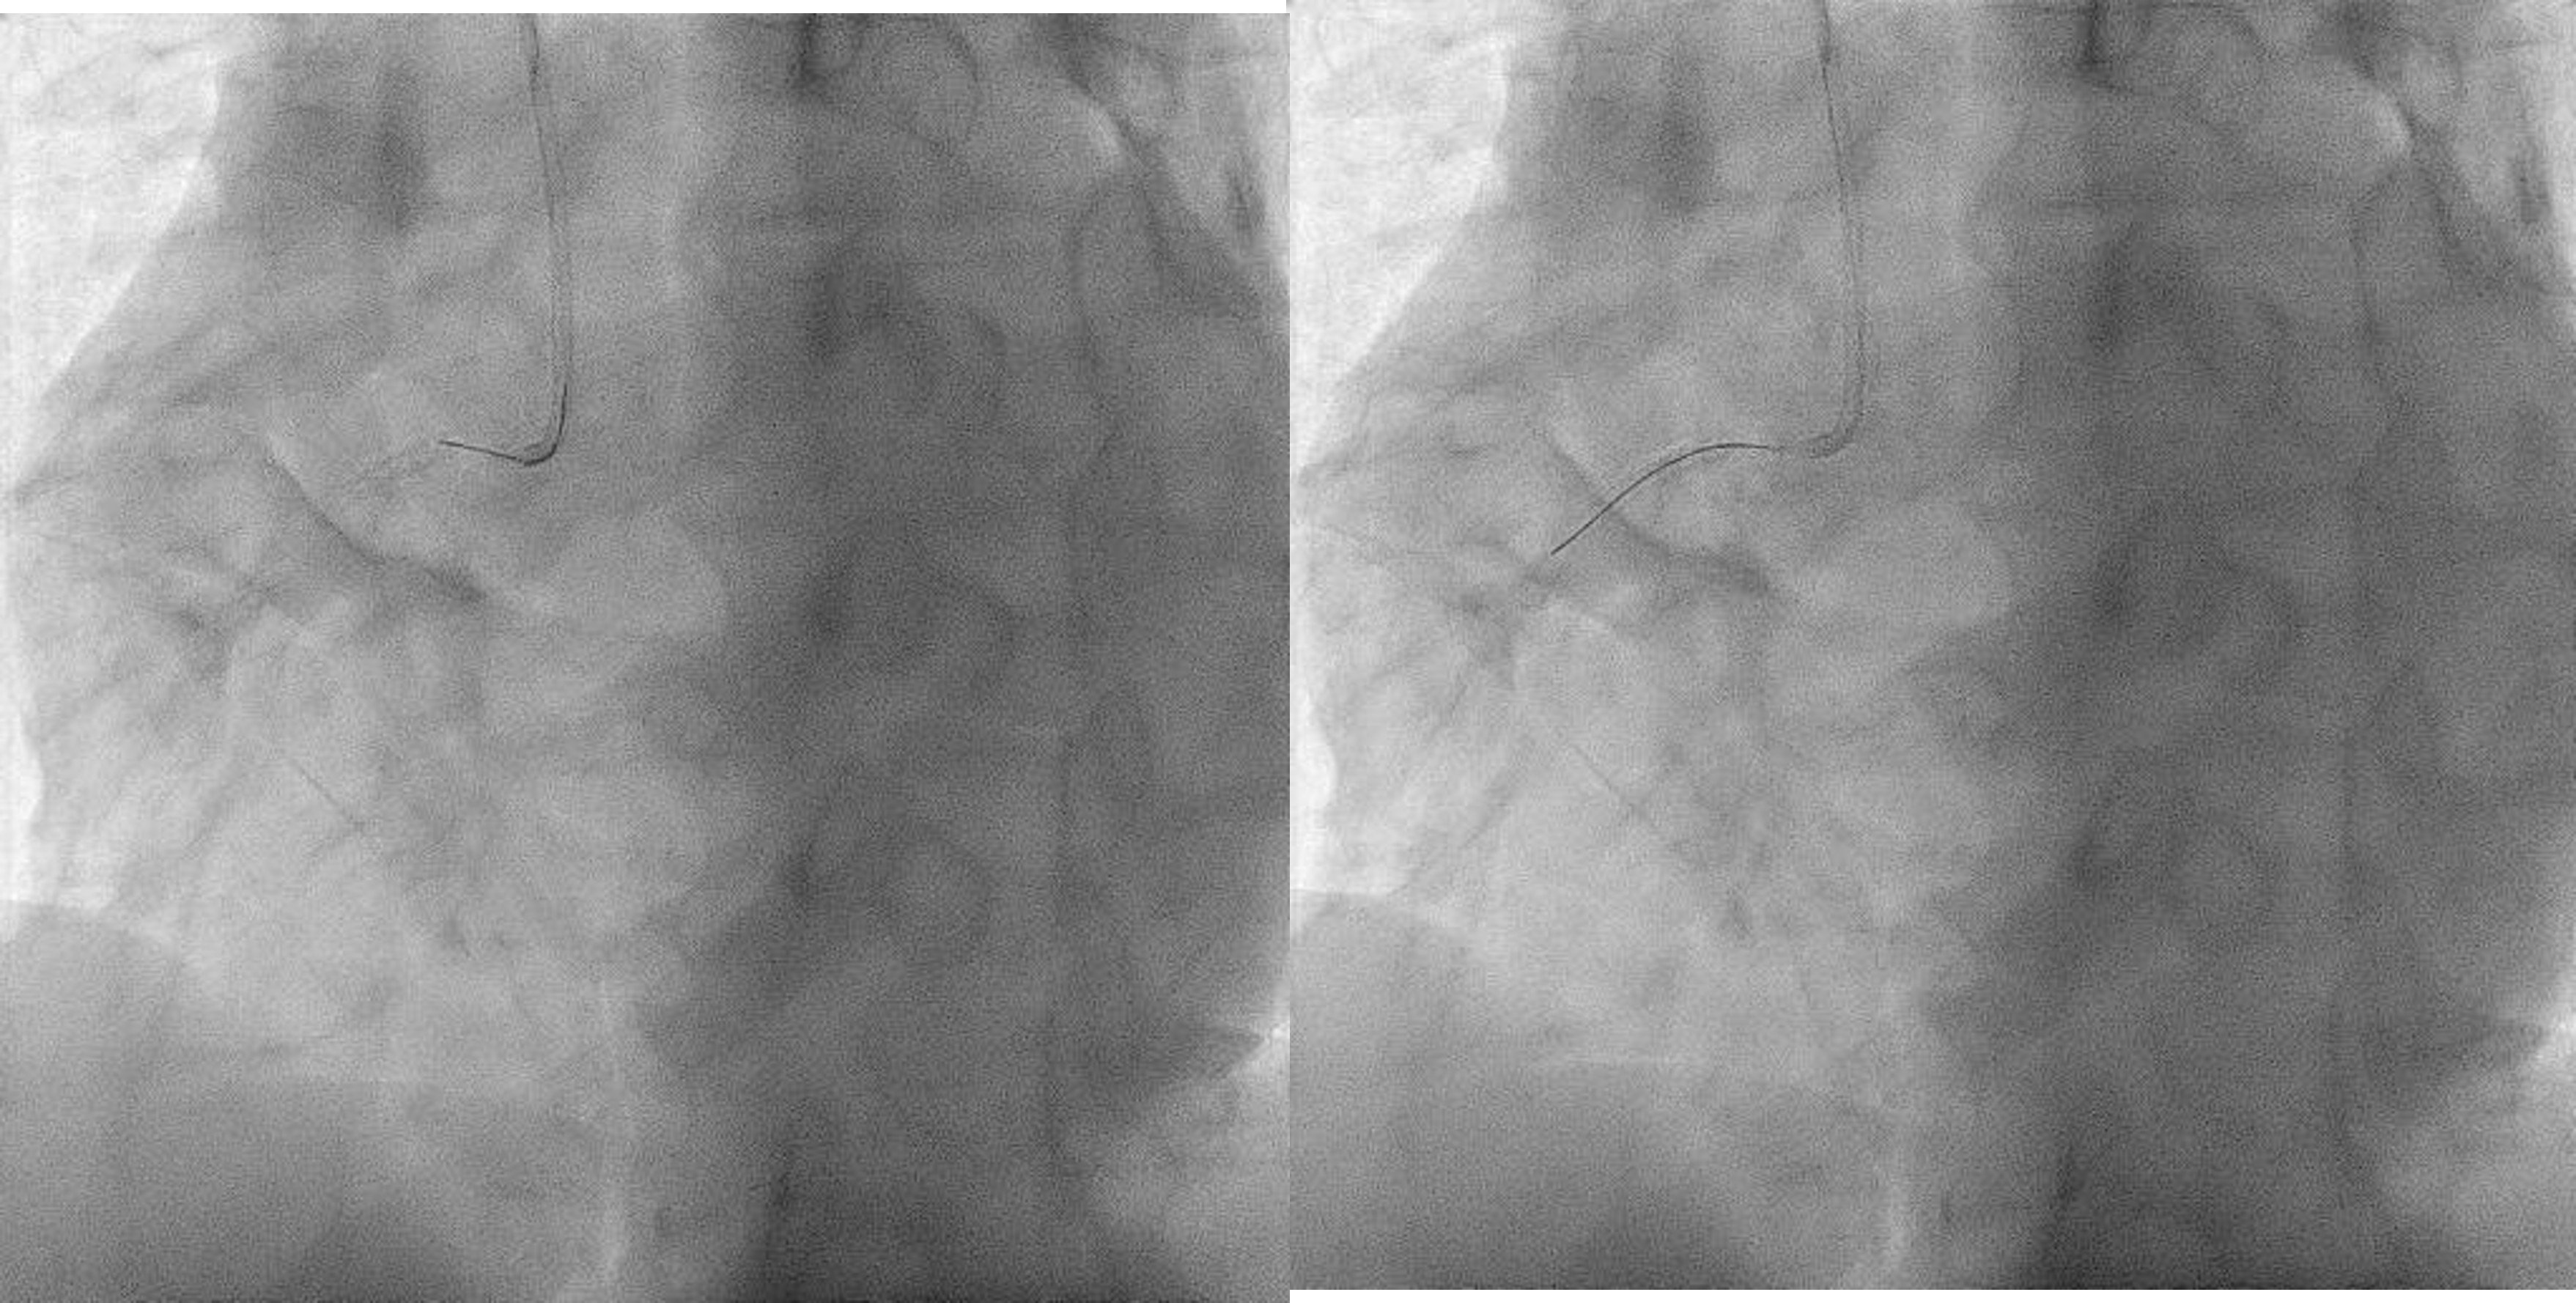

Now for staged PCI to RCA. Attempted engagement with a JR 3.5 6Fr via RRA.Challenges anticipated:1 subclavian tortuosity, noted from past angiography – needing gentle manipulation, avoid femoral access2 poor engagement due to ostium disease3 wiring from outside ( ¡®air-mail¡¯)Lesions are calcifed, diffuse, proximal(ostium RCA) and distal to stented segment - stent not covering ostium.Plan is to IVUS, prepare new lesions, prepare ISR segments then either hybrid DES/DEB or new DES all the way.

Airmail wire into RCA.wmv

Challenges:1 During PCI, ostium lesion causes BP dampening + ST elevations - catheter kept outside ostium during entire PCI2 Wiring was done from outside - 'air mail'ed into the RCA3 Long stent needed delivering - used 'buddy wire' technique to deliver this4 Findings exact ostium was tough - 'buddy wire' converted to 'sepal wire' for better outcome5 During postdilatation, the 'stubborn' nodule at the distal part of stent, was difficult to prepareEven after stenting, IVUS improvement only. Stent boost was used to delineate the calcific nodular area.